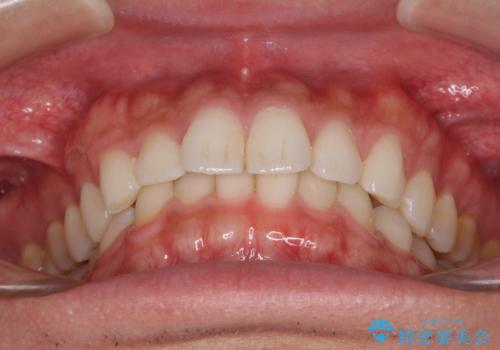

細かい隙間にものがはさまる インビザラインによる矯正治療

- 上下の前歯の隙間を気にして来院された患者様です。

インビザラインを用い、上下歯列のスペースを閉じていくこととしました。

銀行にお勤めのため、突然の転勤により通院が大変な状況となりましたが、インビザラインであれば2-3ヶ月に1度を目安に来院いただき、無事に治療を終えることができました。